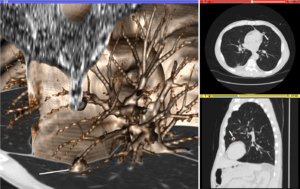

Volume rendering (left), axial cross-section (right top), and sagittal cross-section (right bottom) of a CT image of a subject with multiple nodular lesions (white line) in the lung.

The figure "Visualization of Medical Imaging" illustrates several types of visualization: 1. the display of cross-sections as gray scale images; 2. reformatted views of gray scale images (the sagittal view in this example has a different orientation than the original direction of the image acquisition; and 3. A 3D volume rendering of the same data. The nodular lesion is clearly visible in the different presentations and has been annotated with a white line.